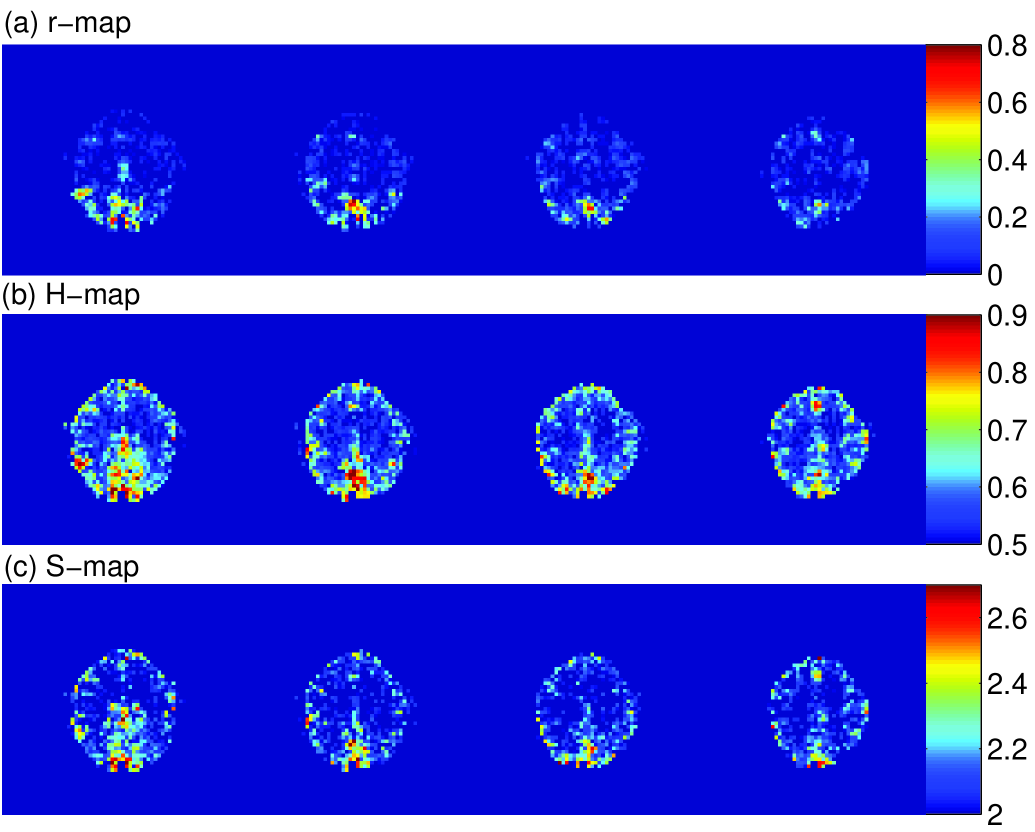

where I¯(x,t)¯𝐼𝑥𝑡\bar{I}(\vec{x},t) is the fMRI signal and ξ(x,t)𝜉𝑥𝑡\xi(\vec{x},t) the residual noise at pixel position x𝑥\vec{x}. We performed the same scaling exponent analysis as before starting from the residual dataset ξ(x,t)𝜉𝑥𝑡\xi(\vec{x},t). As expected the correlation coefficients become vanishingly small and can not serve as a reliable measure anymore, Fig. 3a. With ξ(x,t)𝜉𝑥𝑡\xi(\vec{x},t) as the input, H𝐻H and S𝑆S are shown in Fig. 3b and c. The same areas of activity are recovered. This is a clear sign that ξ(x,t)𝜉𝑥𝑡\xi(\vec{x},t) which is often (wrongly) considered ”white noise” still carries relevant information. One could argue here that if this is the case the model is not yet good enough and has to be improved before discussing statistical significance of activation patterns. However, actually used models are based on linear approaches and can not account for the scaling effects reported here. (ii) Low pass filtering: By applying successive temporal smoothing of the pixel timeseries we find that the scaling effects eventually disappear, and obviously the structure observed here is a characteristics of the noise and not of the low frequency stimulation (signal). (iii) Background noise is white: We find that the background noise (measurement or machine errors) in the signal as observed outside the head fluctuates around H=0.5𝐻0.5H=0.5 (mean and standard deviation: H=0.492±0.046𝐻plus-or-minus0.4920.046H=0.492\pm 0.046), as expected.

Figure 3: Same as previous figure, but starting from the residual dataset ξ(x,t)𝜉𝑥𝑡\xi(\vec{x},t). Clearly the correlation map (a) does not show activation patterns anymore, notice the change in scale compared to the previous figure. H𝐻H and S𝑆S maps, (b) and (c), show the same activated regions and about the same numerical values as in the original data.